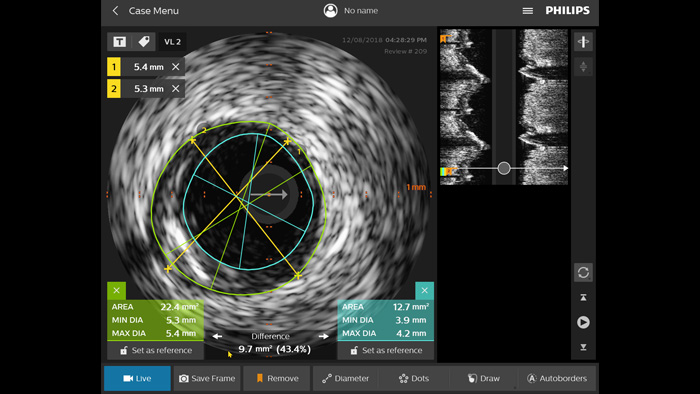

Otimize os resultados dos pacientes utilizando critérios de IVUS padronizados. Em comparação com PCI guiado por angiografia, em todos os pacientes, o ULTIMATE demonstrou que o PCI orientado por IVUS reduz significativamente a revascularização da lesão alvo clinicamente orientada (TLR). Esta vantagem foi sustentada ao longo de três anos. Apenas 1,6% de falha do vaso alvo (TVF) a 12 meses e 4,2% de TVF a 3 anos quando os critérios ideais de PCI orientado por IVUS foram cumpridos.